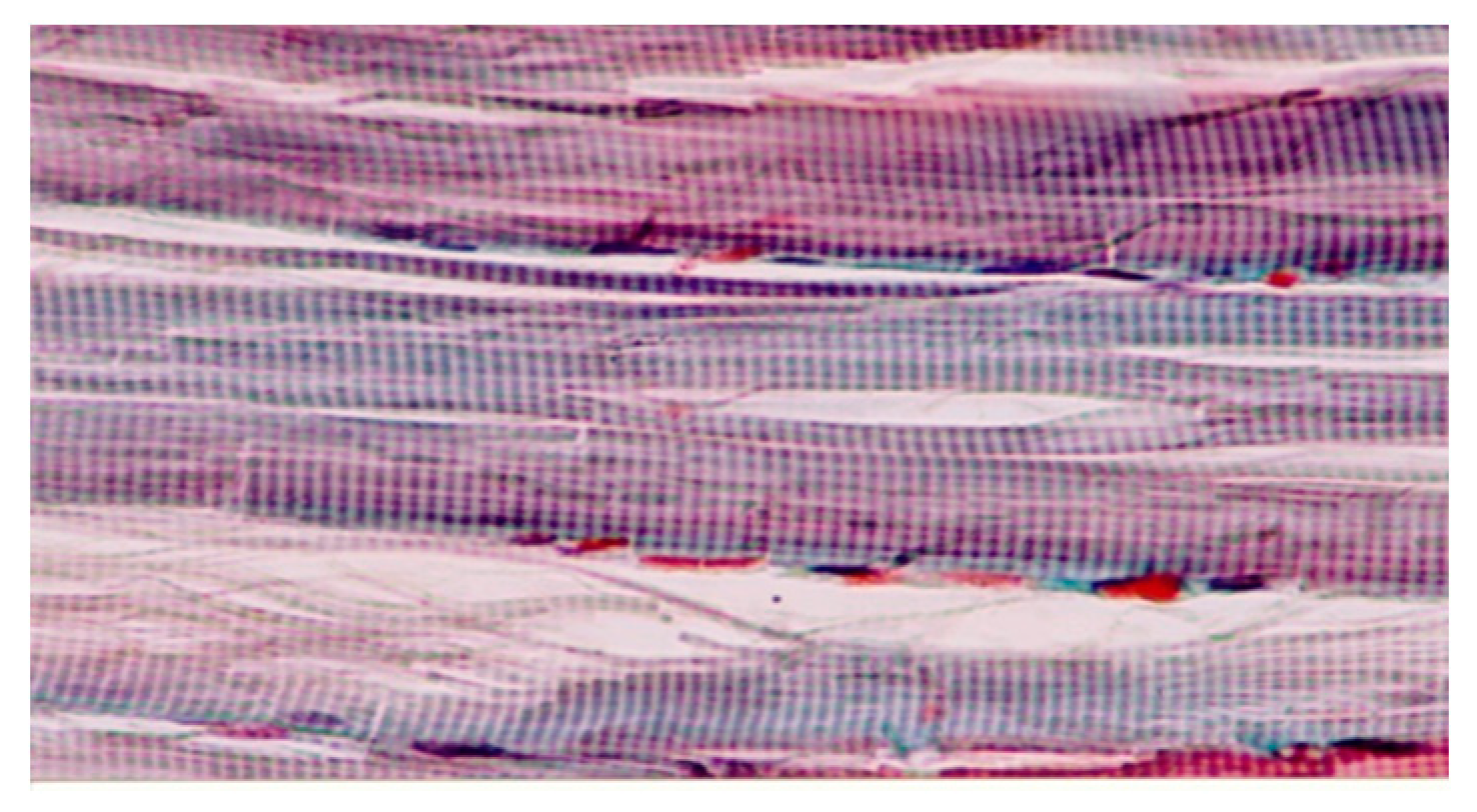

3.2.2. Muscle

3.3. Number of Angiogenesis Vessels/Microscopic field

3.3.2. Muscle